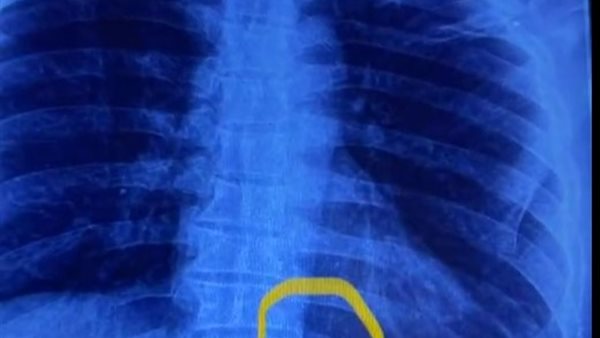

قام المريض بالتوجه إلى مستشفى بنها الجامعي وقام أطباء المستشفى بإجراء الأشعة اللازمة للكشف عن المريض وتبين بالفحوصات والأشعة وجود إبره تنجيد طولية خلف القفص الصدري تم حجز المريض وتقديم كافة الخدمات الطبية.

ونجح فريق من قسم جراحة القلب بمستشفى بنها الجامعي بقيادة الدكتور محمد الجزار من استخراج الإبرة وتبين أنها تقطعت إلى قطع بها صدأ، حيث استمرت بداخل ظهر المريض لأكثر من عامين.